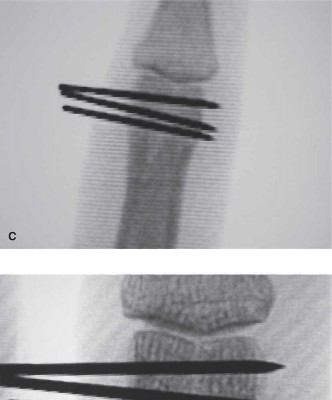

Closed reduction and percutaneous pinning remains the workhorse for extra-articular transverse or short oblique fractures that are reducible but unstable. Reduction is achieved via longitudinal traction, correction of angular deformity, and strict attention to rotational alignment by assessing the digital cascade.

Kirschner wires (typically 0.035 or 0.045 inch) can be introduced in several configurations. Crossed pinning at the fracture site provides excellent torsional stability but risks tethering the lateral bands if placed too dorsally. Alternatively, intramedullary pinning via a retrograde approach through the collateral ligament recesses of the metacarpophalangeal joint or an antegrade approach through the proximal interphalangeal joint can be utilized. Pins are typically left proud and bent to facilitate removal in the clinic at 3 to 4 weeks, once clinical callus is evident.